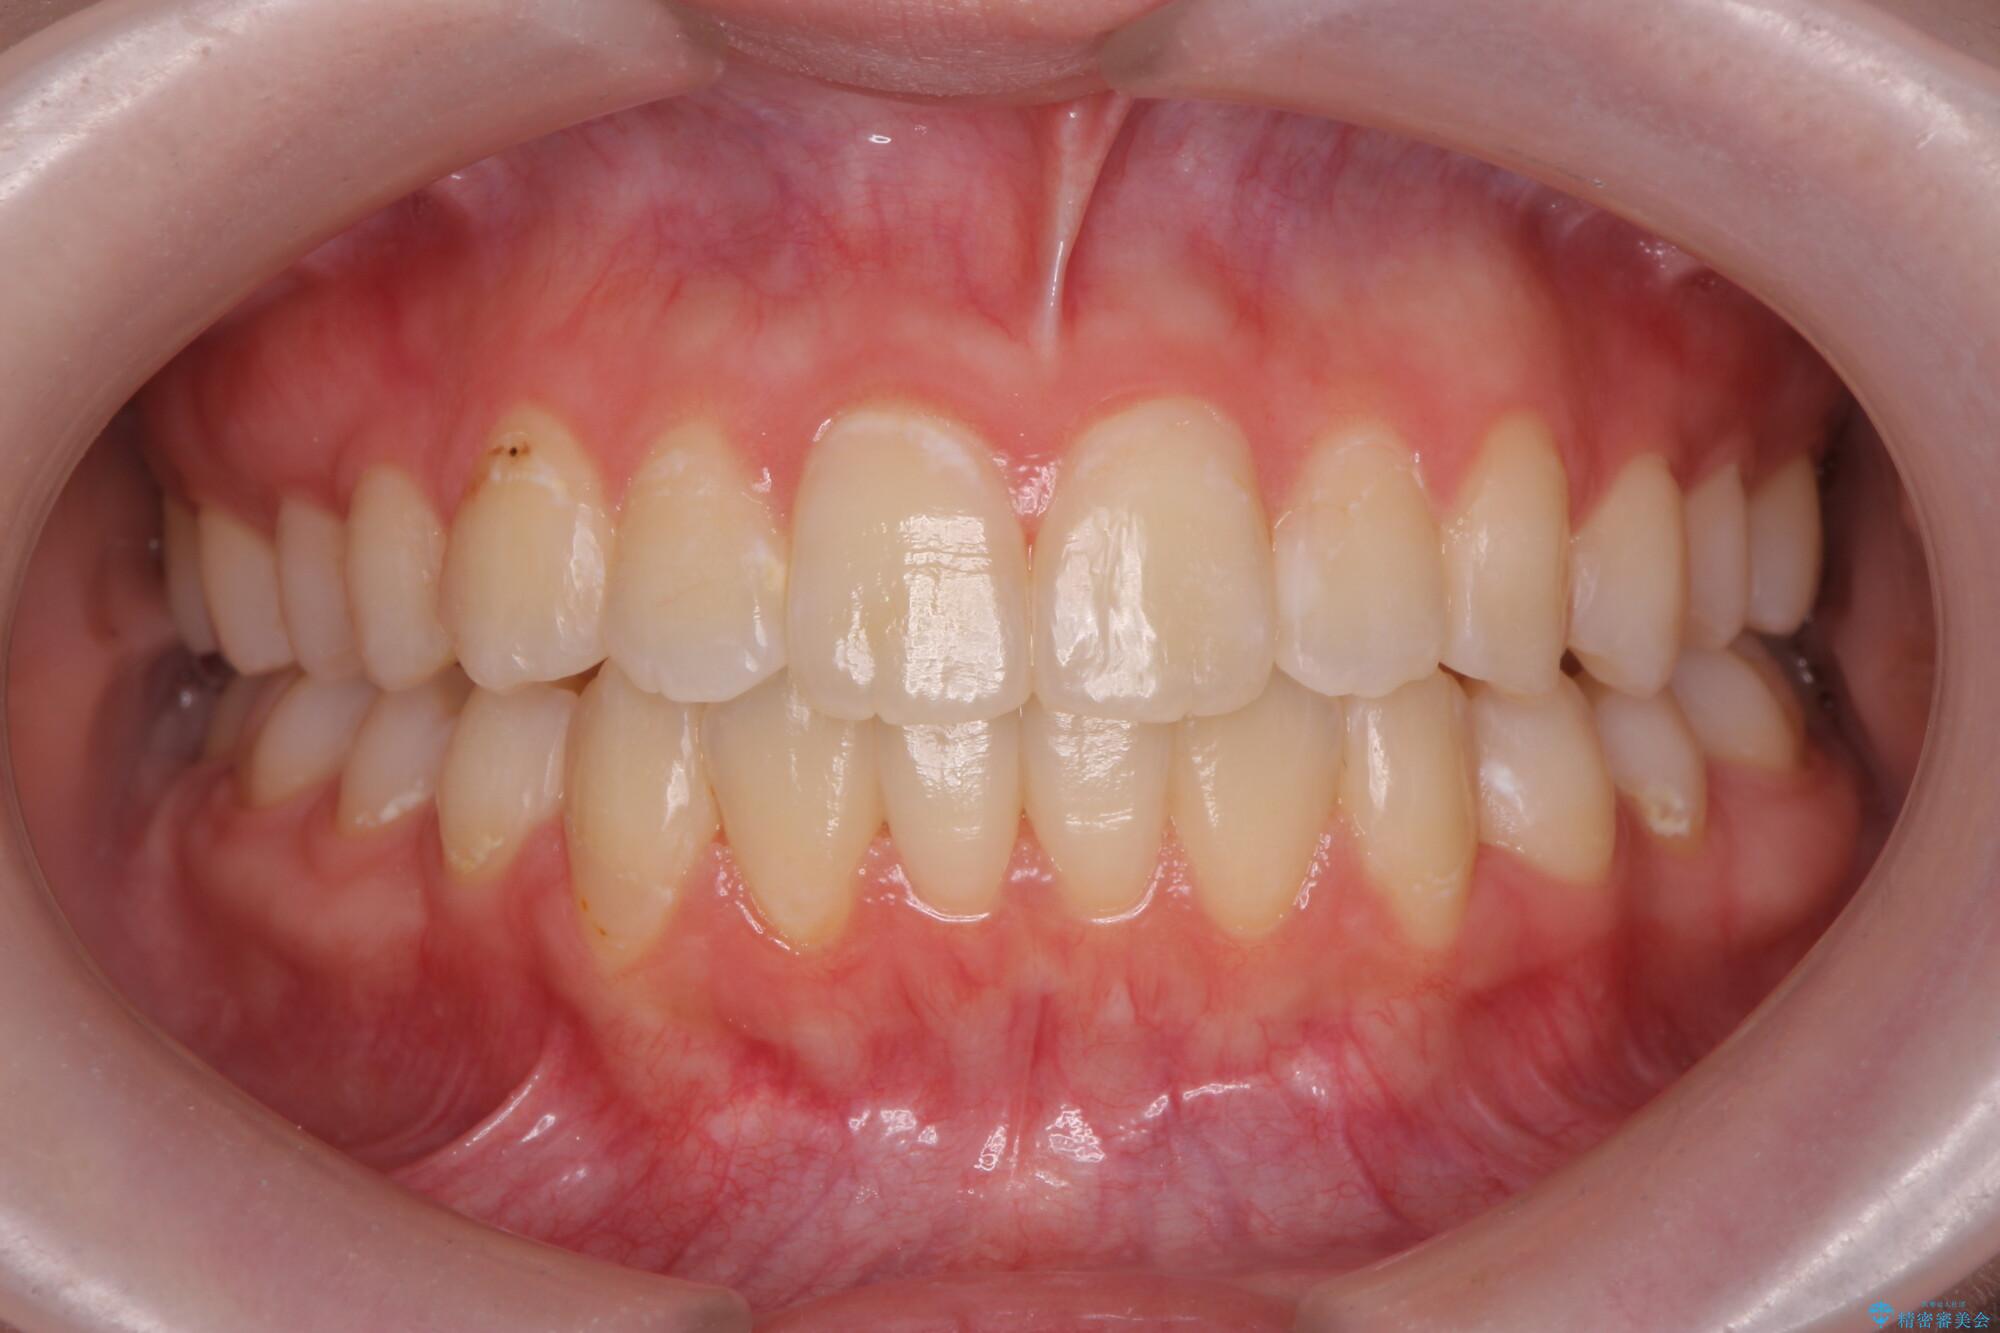

治療前

奥歯のガタつきをマウスピース矯正で改善 治療前画像 奥歯のガタつきをマウスピース矯正で改善 治療前画像 奥歯のガタつきをマウスピース矯正で改善 治療前画像

治療後

奥歯のガタつきをマウスピース矯正で改善 治療後画像 奥歯のガタつきをマウスピース矯正で改善 治療後画像 奥歯のガタつきをマウスピース矯正で改善 治療後画像